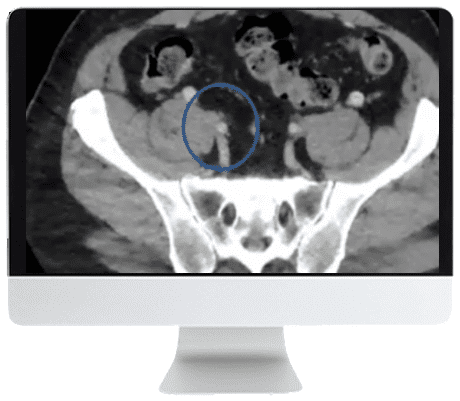

A significant cause of morbidity and mortality for patients of all ages—everything from quality of life impairment to pulmonary embolism—the treatment of venous disease is experiencing rapid progress in both clinical research and device manufacturer approvals. This Online Course will cover the practical impact of these recent trials, techniques, and equipment, while providing an expert look into the future of venous disease therapy.

- Describe the current state and the future of venous thrombectomy/thrombolysis.

- Describe the current state and the future of deep venous stent reconstruction.